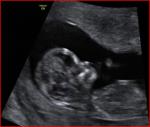

Be gentle but truthful, the doc gave her opinion of BOY so I'm trying to prepare for that. These are the only pics I got and I don't think its the full nub, but I don't know if you need more than that. In the scan I saw a long forked nub but didn't get a pic of it. I couldn't tell the angle though when I saw the complete nub!

Thorz is the nub the sticking straight up bit?

To me it looks huge for a nub, no?

i see a short straight nub... i would lean more girl cause its straight and parallel but i guess its hard to say cause the whole nub is not showing

I think the 'sticking straight up bit' is the cord, the small flat thing below is the nub but I do not think you can make a good guess because I do not think the whole nub is seen, sorry

I don't see a nub. Your doctor may not be guessing based on the nub, so I would be reluctant to just trust her guess. If you saw something long and flat, then it sounds like a girly nub. good luck!

i can't see anything that sounds or rather looks like a boy - bit sticking up is way too big for nub, small thing below maybe a partial nub but i would have said girl especially at that gestation.

No the doc just said, that it is probably a boy, she looked between the legs and only saw cord, but for some reason thought boy. She had no real reason which I thought was weird. I didn't even ask her about the nub theory. Honestly when I saw the real full nub it was long and forked, but I couldn't really tell on the angle, when I saw the print outs I saw that what looked like could have been the nub, looked angled.